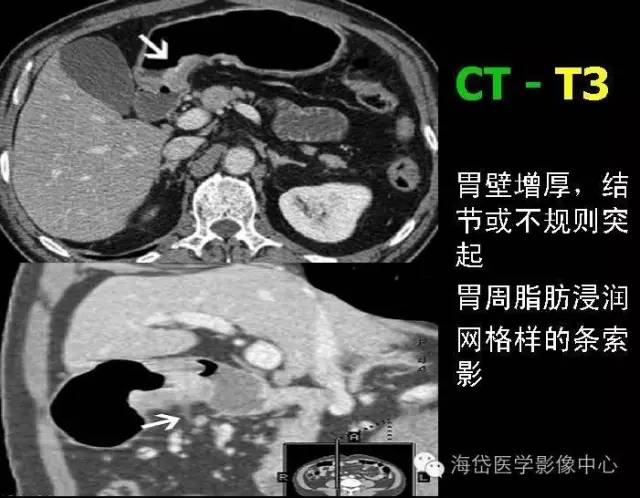

T3 腫瘤侵及漿膜下層。